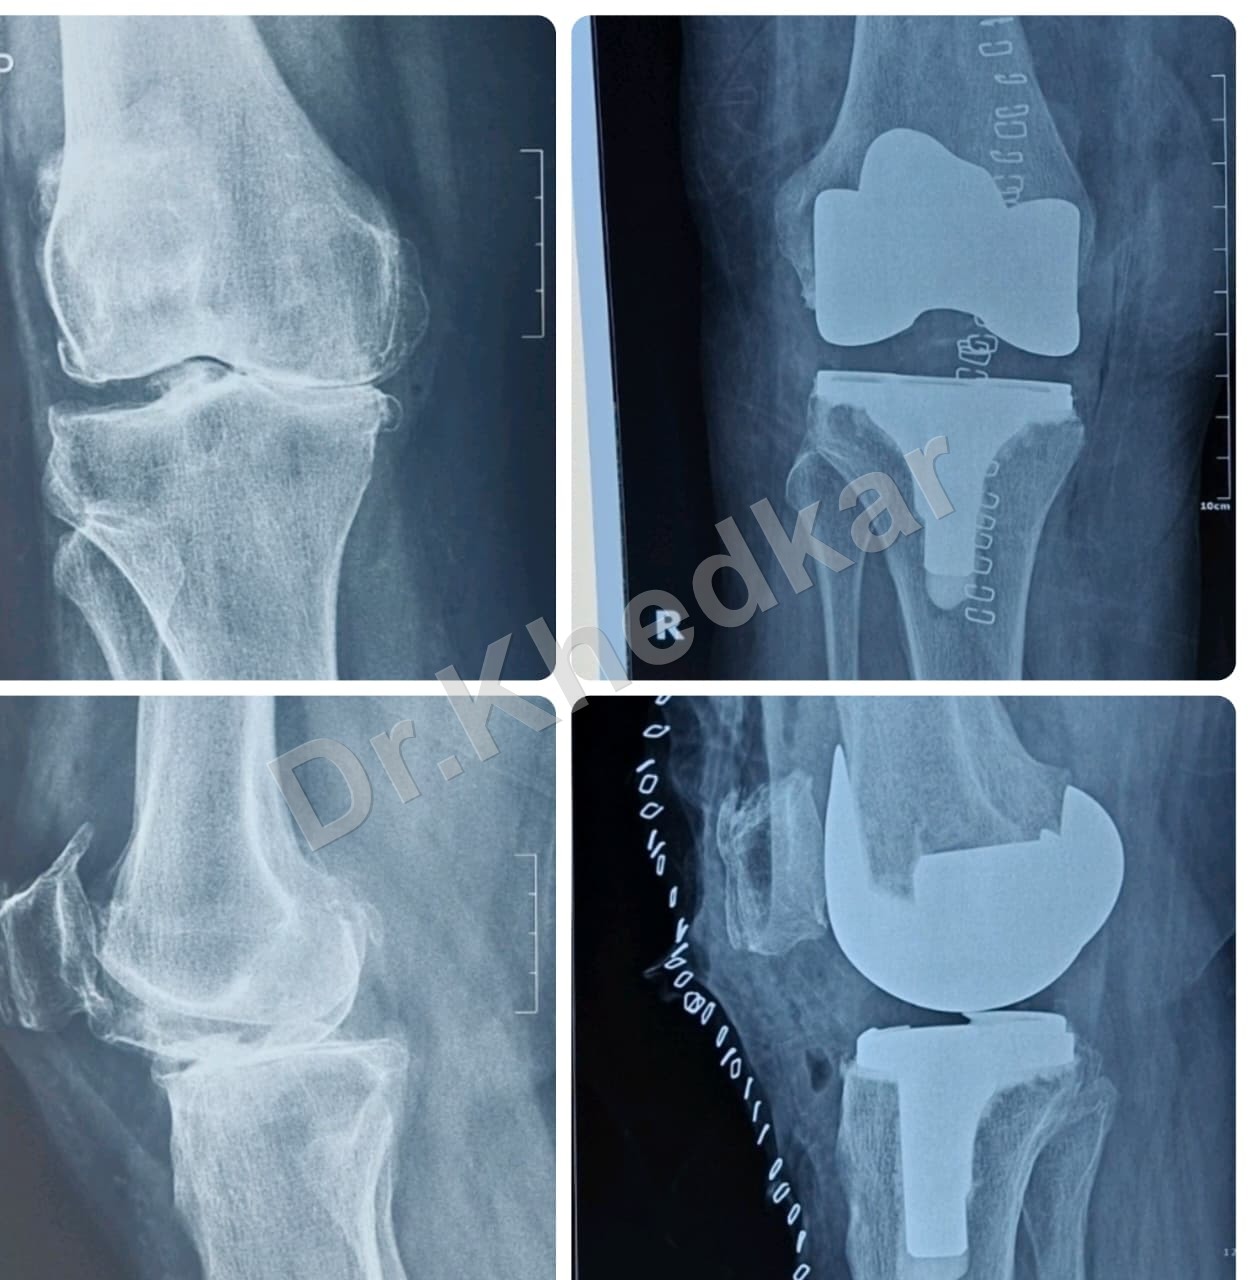

Total Knee Replacement (TKR)

TKR Procedure Thumbnail